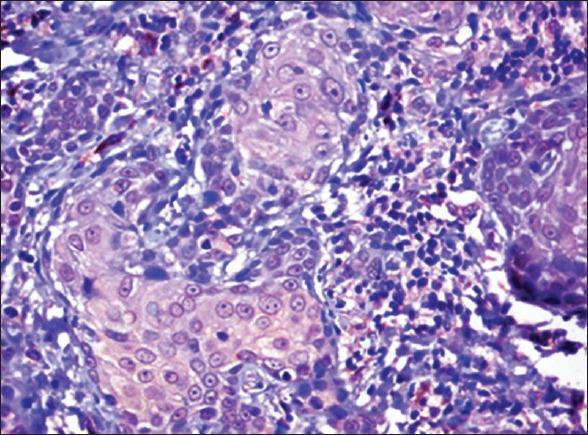

To determine the immunohistochemical (IHC) localization of basement membrane component laminin in histological grades of oral squamous cell carcinoma (OSCC). The purpose of this study was to demonstrate the loss of continuity of the basement membrane in OSCC using an antibody directed against laminin using advanced polymer staining system.

A total of 30 cases of OSCC: 10 cases of well differentiated squamous cell carcinom (WDSCC), 10 cases of moderately differentiated squamous cell carcinoma (MDSCC), and 10 cases of poorly differentiated squamous cell carcinoma (PDSCC) were subjected to heat-induced antigen retrieval method using ethylene-di-amine-tetraacetic acid buffer in a microwave oven. Then the sections were stained with anti-laminin polyclonal antibody and visualized using super sensitive polymer horseradish peroxidase detection system. In each case, the integrity of the basement membrane laminin was assessed by using statistical analysis.

Statistical analysis showed a decreased distribution of laminin from WDSCC to MDSCC to PDSCC (P value 0.0573). The intracytoplasmic staining of laminin gradually increased from WDSCC to MDSCC to PDSCC (P value 0.0198).

WDSCC cases showed more laminin expression in basement membrane around the tumor islands and less loss of continuity compared to MDSCC and PDSCC cases suggesting a greater enzymatic degradation of basement membrane components in MDSCC and PDSCC than WDSCC. The loss of structural basement membrane laminin and the presence of laminin in the tumor cells of PDSCC cases suggest that laminin helps in tumor invasion. The expression of laminin in the basement membrane may be a useful parameter to evaluate tumor histologic differentiation and aggressiveness.